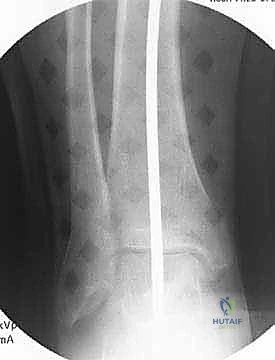

تُعد الأشعة السينية (X-rays) الممتدة من الحوض إلى الكاحل (Scanogram) ضرورية جداً لحساب زاوية التقوس بدقة وتحديد مقدار التعديل المطلوب جراحياً.

قبل العملية، يتم قياس زوايا الركبة بدقة متناهية. كل درجة من درجات التعديل يتم حسابها مسبقاً.

استخدام التخطيط الرقمي يضمن عدم حدوث تصحيح مفرط (Over-correction) أو تصحيح ناقص (Under-correction)، وهو ما يميز الجراح الخبير عن غيره.

يتم فتح العظم تدريجياً وببطء شديد حتى الوصول إلى الزاوية التي تم حسابها في التخطيط الرقمي قبل الجراحة.